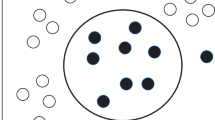

Covid-19 is a serious disease caused by the Sars-CoV-2 virus that has been first reported in China at late 2019 and has rapidly spread around the world. As the virus affects mostly the lungs, chest X-rays are one of the safest and most accessible ways of diagnosing the infection. In this paper, we propose the use of an approach for detecting Covid-19 in chest X-ray images through the extraction and classification of local and global percolation-based features. The method was applied in two datasets: one containing 2,002 segmented samples split into two classes (Covid-19 and Healthy); and another containing 1,125 non-segmented samples split into three classes (Covid-19, Healthy and Pneumonia). The 48 obtained percolation features were given as input to six different classifiers and then AUC and accuracy values were evaluated. We employed the 10-fold cross-validation method and evaluated the lesion sub-types with binary and multiclass classification using the Hermite Polynomial classifier, which had never been employed in this context. This classifier provided the best overall results when compared to other five machine learning algorithms. These results based in the association of percolation features and Hermite polynomial can contribute to the detection of the lesions by supporting specialists in clinical practices.

Roberto, G.F., Nascimento, M.Z., Martins, A.S., Tosta, T.A., Faria, P.R., Neves, L.A.: Classification of breast and colorectal tumors based on percolation of color normalized images. Comput. Graph. 84, 134–143 (2019)